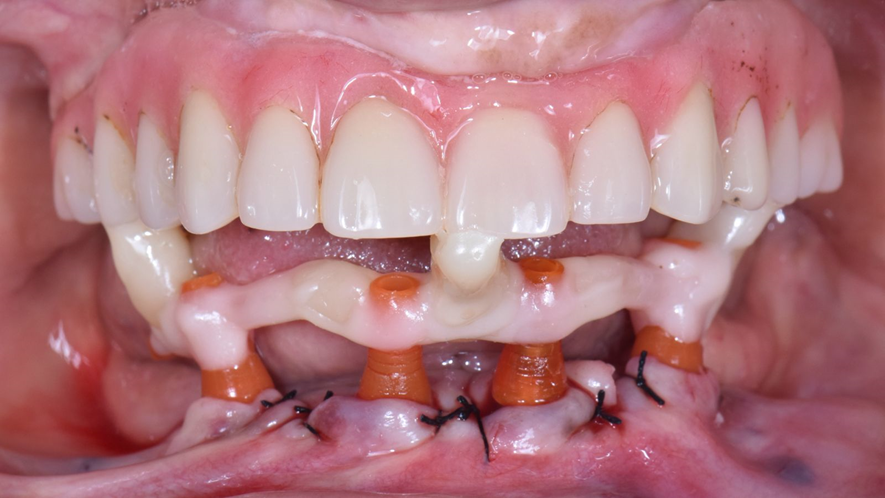

Com o escaneamento validado, demos sequência à confecção da prótese protocolo final.

A utilização do escaneamento intraoral na prática clínica torna os procedimentos mais rápidos e mais confortáveis para o paciente, eliminando as etapas de moldagem em um rebordo recém-operado. E os scan bodies de arco total Implacil Osstem facilitaram o escaneamento de arcos totais desdentados, garantindo precisão nos processos.